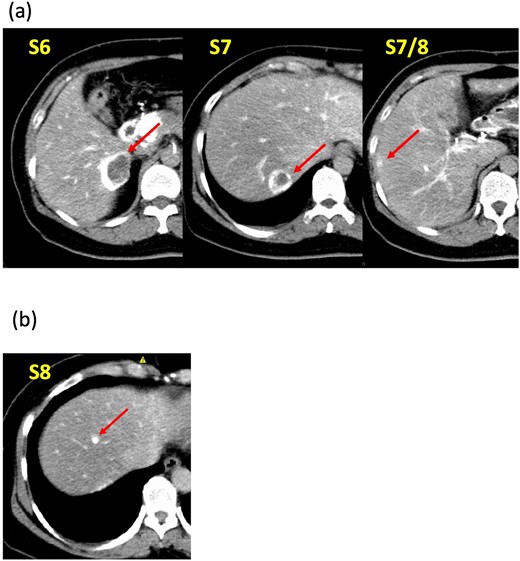

A 52-year-old woman was admitted to our hospital for the evaluation and treatment of multiple cystic liver tumors. Two years earlier, dynamic computed tomography (CT) had detected multiple cystic tumors in segments 6 (S6) and 7 (S7), which were subsequently monitored (Fig. 1a). The patient showed no symptoms; laboratory tests for tumor markers such as α-fetoprotein, protein induced by vitamin K absence or antagonist-II, carcinoembryonic antigen, and carbohydrate antigen 19–9 were within normal ranges. Dynamic CT identified two low-density tumors with peripheral enhancement in the portal phase, featuring cyst-like internal septa (Fig. 1b), which showed slow enlargement over 2 years. Magnetic resonance imaging (MRI) using gadoxetic acid (gadolinium-ethoxybenzyl-diethylenetriamine pentaacetic acid; EOB Primovist®) revealed that tumors appeared as low intensity signals on T1-weighted imaging and high intensity signals on T2-weighted imaging and diffusion-weighted imaging. Additionally, a 7-mm lesion was observed at the S7/8 boundary (Fig. 2a and b). Positron emission tomography-CT (PET-CT) showed abnormal uptake in S6 and S7 tumors but not in the S7/8 lesion (Fig. 3). CT during hepatic arteriography (CTHA) demonstrated well-contrasted tumors at the periphery, with no contrast enhancement in the center (Fig. 4a). Moreover, CTHA detected a new tumor in S8, displaying clear and uniform contrast but not visible with other imaging modalities (Fig. 4b).

Dynamic computed tomography (CT) findings. (a) Two years ago, cystic tumors were detected as low-density lesions surrounded by contrasting tissue in segments 6 (S6) and 7 (S7). (b) Preoperative CT shows both tumors had enlarged slightly.